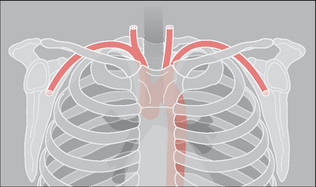

Figure 32.1 There is a close relationship between the subclavian artery and the posterior aspect of the first rib and the clavicle. The first rib is very strong. If an injury causes a fracture of this rib then it should be assumed that a very powerful blow has been sustained.

Double check ribs 1–3, the clavicles, and the scapulae7,8

image A fracture involving ribs 1–3 usually results from a very severe force. Important soft tissue and vascular injuries are potential complications. These include:

image Arterial or venous rupture; arising from the close relationship of the first rib to the subclavian vessels.

image A fracture of the clavicle or scapula may injure the subclavian artery.